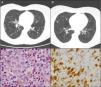

The patient was a 50-year-old woman who smoked 20 cigarettes/day. She had been diagnosed with seropositive (rheumatoid factor [RF] and anti-cyclic citrullinated peptide antibodies [anti-CCP]), erosive rheumatoid arthritis (RA) in 1999. She was being treated with methotrexate (MTX) since 2000, in combination with salazopyrin and hydroxychloroquine since February 2009, at which time, she had achieved complete remission. In March 2010, in relation to a self-limiting case of a cold, her primary care physician had asked for a chest radiograph, which showed possible images of nodules, predominantly in the upper lobes. The patient was asymptomatic and the physical examination was normal. She had an immunological study in which she tested positive for RF and anti-CCP and negative for antinuclear antibodies and antineutrophil cytoplasmic antibodies; the Mantoux text was positive, and chest computed tomography revealed multiple bilateral pulmonary nodules measuring about 0.5cm, some showing cavitation, especially in images from the upper and middle lobes, but the lower lobes were also involved (Fig. 1A). The bronchoscopy was normal, with negative results in the smear, bronchoalveolar lavage fluid culture and cytology of the bronchial aspirate for malignant cells. The patient was referred to undergo lung biopsy. Videothoracoscopy revealed that the lung parenchyma had small scattered subpleural lesions, and the pathological study showed the presence of foamy histiocytes with grooved nuclei, with other multinucleated and somewhat elongated histiocytes occupying the alveolar spaces (Fig. 1C). Immunohistochemical techniques identified cells that were positive for CD1a (Fig. 1D) and for S100, as well as langerin in the histiocytes described, all of which was consistent with Langerhans cell (LC) histiocytosis (LCH). At that time, it was recommended that she quit smoking and the same immunosuppressive therapy was maintained. During that entire period, she had no joint or respiratory symptoms and underwent radiographic follow-up 6 months later. The images showed residual pulmonary cysts and the nodules had disappeared (Fig. 1B). After 5 years of follow-up with no new incidences, the patient continues to receive triple immunosuppressive therapy.